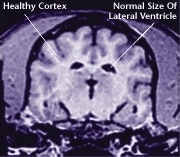

The aging process attacks all body systems and organs in a dog, including the brain. The result is a loss of brain function, and often, the appearance of behavioral changes that were not present in a dog’s younger years.

![]() Healthy Older Brain | ![]() Older Brain with Damage |

| MRI scans show loss of brain tissue in affected dogs. Note: MRI scans are not harmful to dogs. | |